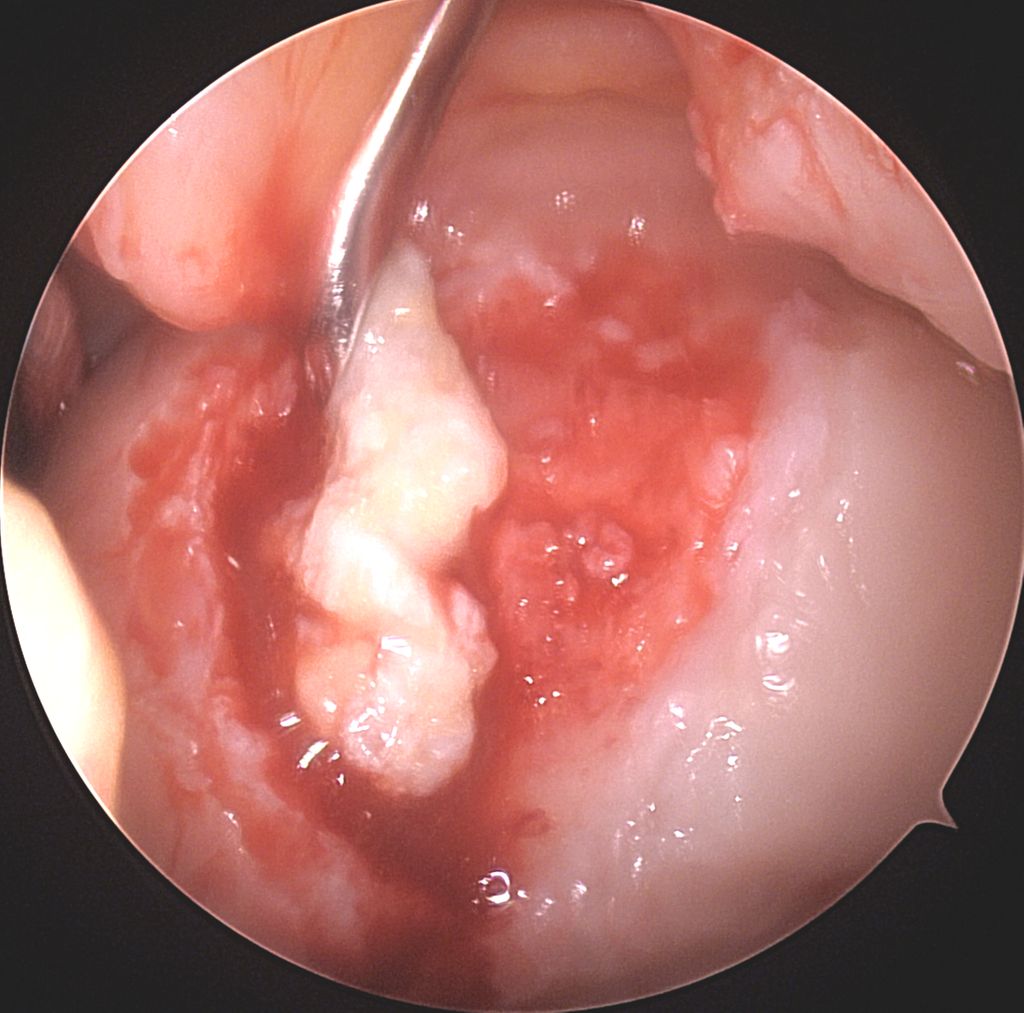

Abb. 1d: Intraoperative, rein arthroskopische Trokar-Applikation der autologen Knorpelfragmente in den Defekt an der medialen Femurkondyle vermischt mit PRP im Rahmen der Minced-Cartilage-Prozedur

Abb. 1e: Intraoperatives, arthroskopisches Bild des Endresultates nach Applikation der autologen Knorpelfragmente in den Defekt an der medialen Femurkondyle. Nach Aushärten des körpereigenen Fibrins wird keine weitere stabilisierende Membran benötigt